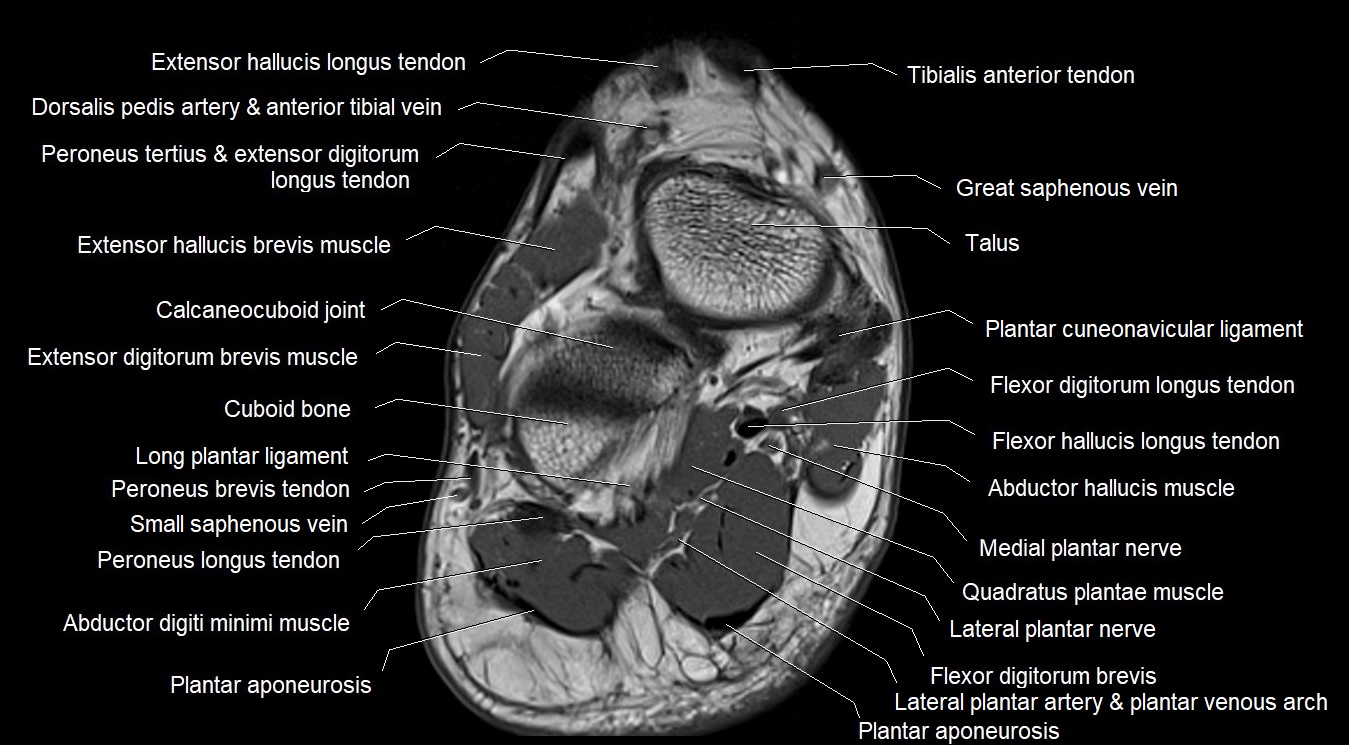

MRI image